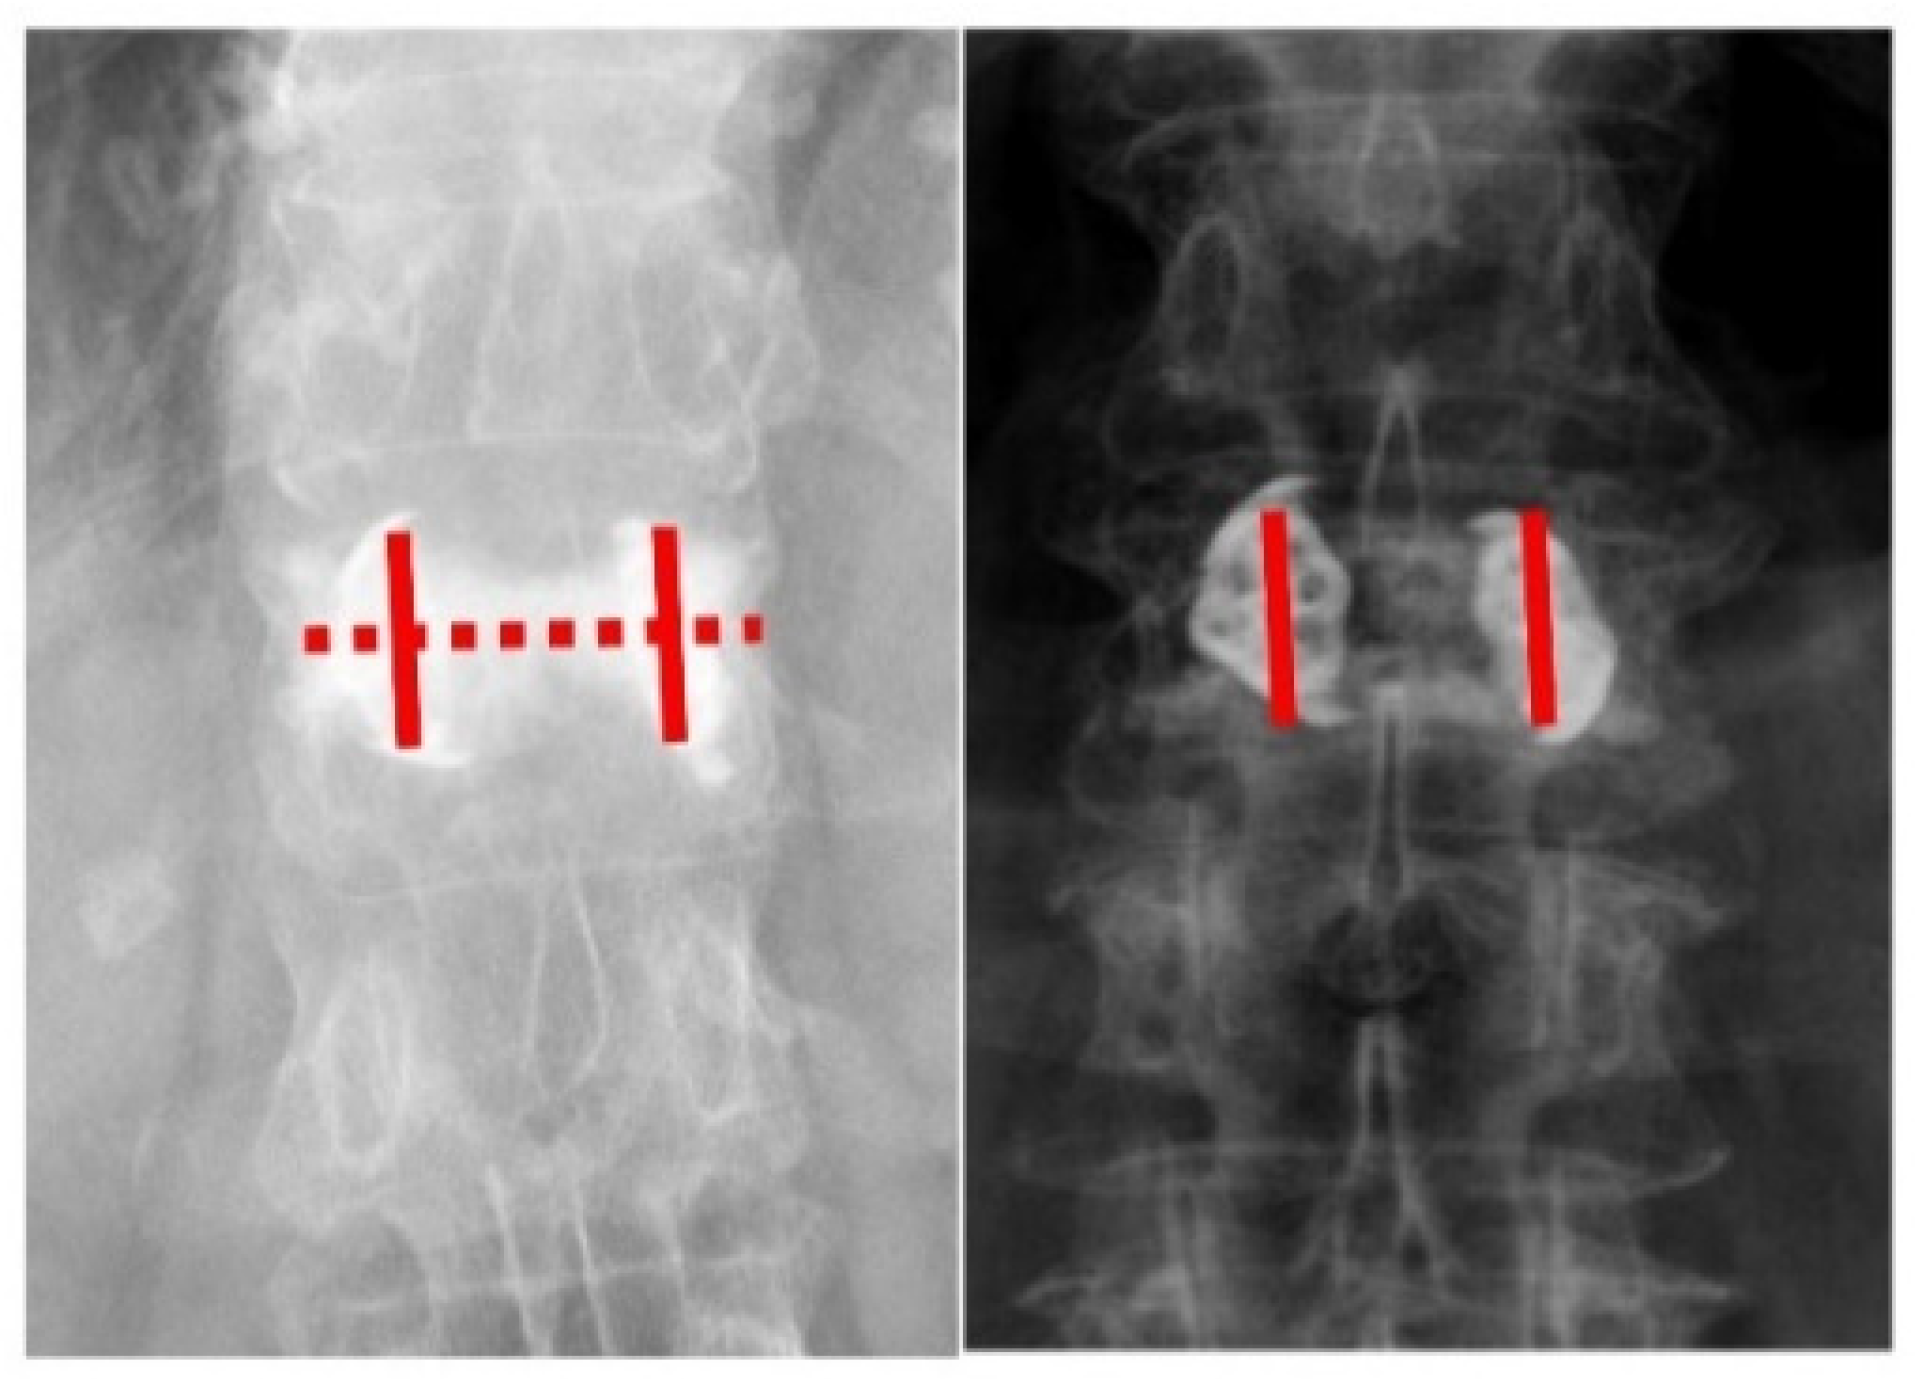

“Double Cross Sign” Could Be an Indicator of an Adequate Amount of Bone Cement in Kyphoplasty with the SpineJack System: A Retrospective Study

| Angle change between devices (mL) | 3.7 ± 4.3 | 9 ± 4.7 | p = 0.002 * |